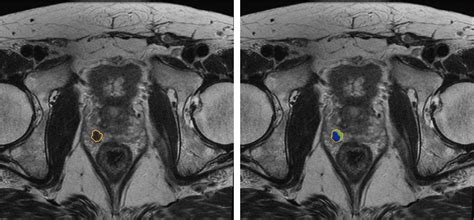

• Multiparametric MRI (mpMRI): This technique combines multiple MRI sequences, including T2-weighted imaging, diffusion-weighted imaging (DWI), and dynamic contrast-enhanced (DCE) imaging, to provide a comprehensive evaluation of the prostate.

• Prostate Imaging Reporting and Data System (PI-RADS): This standardized reporting system helps radiologists interpret MRI findings and classify the likelihood of clinically significant prostate cancer.

• Fusion Biopsy: This technique combines MRI images with real-time ultrasound guidance to perform targeted biopsies, improving the accuracy of cancer detection.